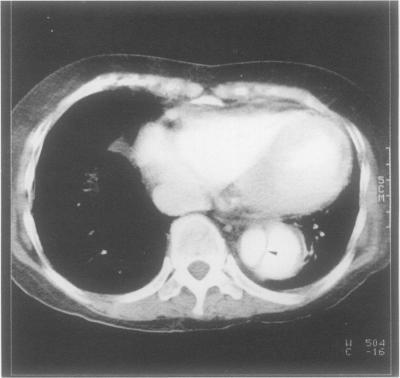

A case of autoimmune thyroiditis after long term treatment with lithium is described in a 29 year old Japanese woman with manic depression. Positive serum antithyroglobulin and antimicrosomal antibodies, diffuse goitre, and microscopic chronic thyroiditis, as well as the clinical history of long term lithium treatment were suggestive of lithium associated autoimmune thyroiditis. Microscopically, there was a mild degree of interstitial fibrosis and a moderate degree of lymphocytic infiltration. Some areas showed a moderate degree of stromal fibrosis and atrophic thyroid follicles. Lymphoid follicles with germinal centres, disrupted thyroid follicles with lymphocytic infiltration, and Hürthle cells were also observed. The differential diagnosis in patients presenting with these histological features includes painless (silent) thyroiditis, autoimmune thyroiditis and lithium associated autoimmune thyroiditis. A detailed clinical history is essential if the correct diagnosis is to be reached.

一名患有躁郁症的29岁日本女性,在长期接受锂治疗后出现了自身免疫性甲状腺炎。血清抗甲状腺球蛋白和抗微粒体抗体呈阳性、弥漫性甲状腺肿、显微镜下的慢性甲状腺炎以及长期锂治疗的临床病史提示为锂相关性自身免疫性甲状腺炎。显微镜下可见轻度间质纤维化和中度淋巴细胞浸润。部分区域显示中度间质纤维化和萎缩性甲状腺滤泡。还观察到有生发中心的淋巴滤泡、淋巴细胞浸润的破裂甲状腺滤泡以及许特莱细胞。具有这些组织学特征的患者的鉴别诊断包括无痛性(寂静性)甲状腺炎、自身免疫性甲状腺炎和锂相关性自身免疫性甲状腺炎。若要做出正确诊断,详细的临床病史至关重要。